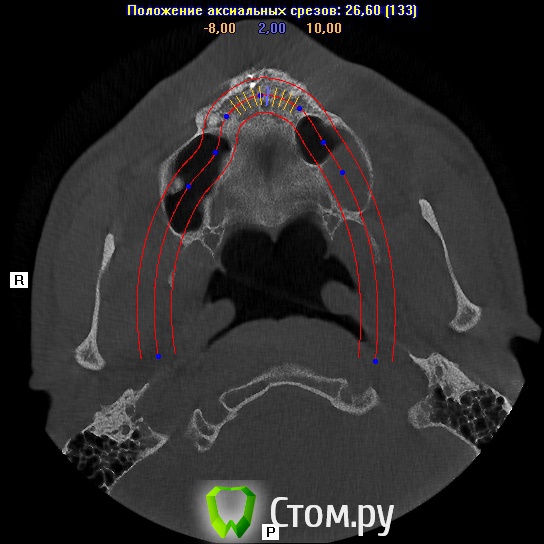

sergey765 Опубликовано 11 июня, 2014 Автор Поделиться Опубликовано 11 июня, 2014 посмотрите пожалуйста КТ. Ссылка на комментарий

sergey765 Опубликовано 11 июня, 2014 Автор Поделиться Опубликовано 11 июня, 2014 могу вам ещё снимков выложить.их довига. беспокаят меня боли после удаления .прошло 5 недель. снимки девушка лет 20 эти смотрела. сказала что у меня там инфекции дофига. типа давай я тебя на понедельник к хирургу запишу. он ранку вскроет. прочистит Ссылка на комментарий

Bier Опубликовано 11 июня, 2014 Поделиться Опубликовано 11 июня, 2014 это все не информативные кадры, в прикрепленных темах есть инструкция, выкладывайте КТ целиком, наш рентгенолог скачает и выложит срезы. 3 Ссылка на комментарий

sergey765 Опубликовано 12 июня, 2014 Автор Поделиться Опубликовано 12 июня, 2014 хорошо сейчас скидываю весь диск в рар архиве в файлообменник. люди добрые пожалуйста скачайте посмотрите. умоляю на коленях. ситуация у меня крайне серьезная. мне нужно чтобы хороший хирург посмотрел. в долгу не останусь. и если что у меня сильно там серьезное приеду к вам в клинику в москву/питер. а там что-то полюбас будет..... вчера когда делал КТ в частной клинике девочка (лет 20) смотрела, нифига вроде не поняла, сказала только у меня там инфекции полно (где там я не понял) и лунка удаленного зуба не заживает типа надо хирургу показать он вскроет прочистит т.е возможно когда мне зуб удаляли не прочистили там ничего... сейчас меня беспокоят боли в районе подбородка. самочувствие моё плохое. с кровати почти не встаю. все написано в начале данной темы.умоляю скачайте посмотрите. томограмма сделана программой iCATVision Ссылка на комментарий